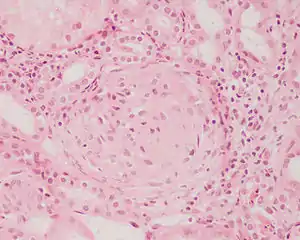

Rapidly progressive glomerulonephritis, also known as crescentic GN, is characterised by a rapid, progressive deterioration in kidney function. People with rapidly progressive glomerulonephritis may present with a nephritic syndrome. In management, steroid therapy is sometimes used, although the prognosis remains poor.[9] Three main subtypes are recognised:[4]: 557–558

Histopathologically, the majority of glomeruli present "crescents". Formation of crescents is initiated by passage of fibrin into the Bowman space as a result of increased permeability of glomerular basement membrane. Fibrin stimulates the proliferation of endothelial cells of Bowman capsule, and an influx of monocytes. Rapid growing and fibrosis of crescents compresses the capillary loops and decreases the Bowman space, which leads to kidney failure within weeks or months.